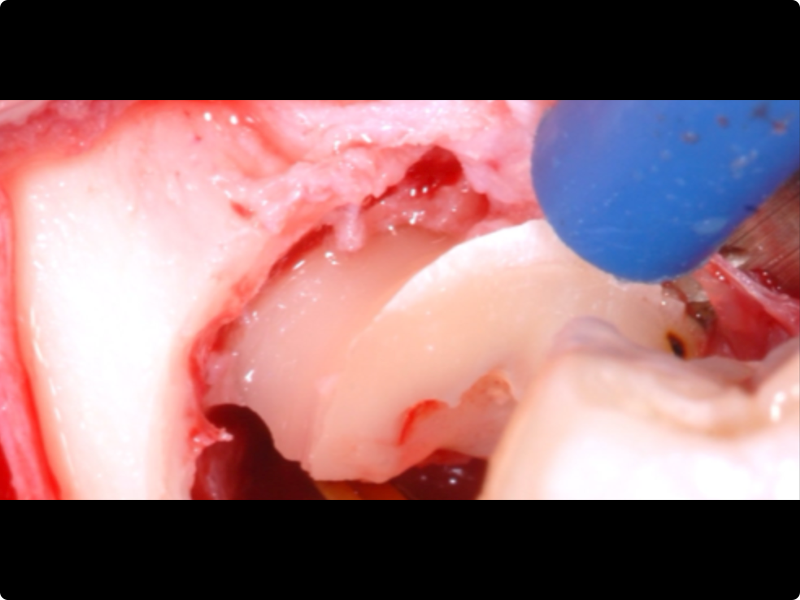

- Odontotomy and rhizotomy.

- Dislocation and extraction.

Clinical cases of impacted third molar surgery and explanatory videos

- Traditional technique exercises with rotary burs (teeth kit by Dr. A. Borgonovo).

- Sonic technique exercises with inserts dedicated to the surgery of impacted teeth.